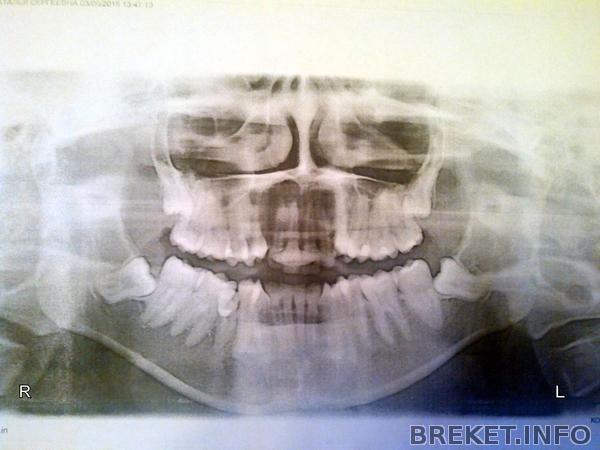

Ситуация такая: большая скученность зубов, высокое положение клыков, НЧ смещена вправо из-за того, что правая 5ка выбилась из зубного ряда. Зубы мудрости (8ки) ретинированные и дистопированные. Была на консультации у 3х ортодонтов, мнения разделились: двое при беглом осмотре без расчетов отправляют на удаление ВЧ 4ок и НЧ 5ок объясняя это тем, что нет места для зубов, а без удаления будет неправильный прикус, зубы выдвинутся вперед и под углом. После удаления 4ок и 5ок якобы будет место и для 8ок если они прорежутся. Другой ортодонт говорит, что ни в коем случае нельзя удалять 4ки и 5ки, необходимо удаление только всех 8ок, а 4кии 5ки обычно удаляют чтобы ускорить процесс лечения. Саму длительность лечения обещают в 1.5-2 года. Как в данном случае лучше поступить и к кому прислушаться? Все зубы здоровые, не хочется их терять.